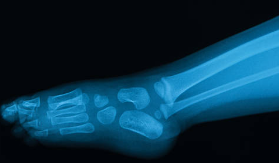

1. 관절염과 통증 완화

글루코사민의 효능 중 가장 잘 알려진 것은 골관절염과 관련된 통증을 줄이는 능력입니다. 글루코사민은 연골의 구성 성분으로 작용하여, 연골이 마모되는 것을 늦추고 기존 연골의 회복을 도와 통증과 뻣뻣함을 감소시킵니다. 이는 연골 밑의 뼈가 서로 마찰되는 것을 방지하여, 관절의 유연성을 향상시키고 일상 활동 시 통증을 감소시키는 데 도움을 줍니다.

2. 연골 건강 증진

글루코사민은 연골 세포의 성장을 촉진하고, 연골이 자연적으로 마모되는 과정을 늦춥니다. 연골 조직을 강화하고 수분과 영양을 유지하는 데 필수적인 역할을 함으로써, 관절의 쿠션 역할을 효과적으로 수행할 수 있도록 돕습니다.